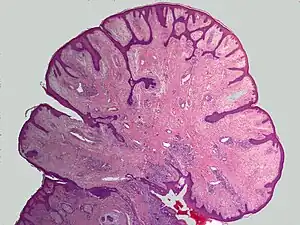

AGF lesions share common macroscopic (i.e. gross) and microscopic appearances. Grossly, AGF lesions consist of multiple papules, one or more skin-colored to erythematous, dome-shaped nodules, or usually just a single tumor. Microscopically, they consist of spindle-shaped and stellate-shaped cells centered around dilated and thin-walled blood vessels in a background of coarse bundles of collagen (i.e. the main fibrous component of connective tissue).[1] Angiofibromas have been divided into different types but commonly a specific type was given multiple and very different names in different studies.[1] The following list gives a brief description of the AFG types and their alternate names.